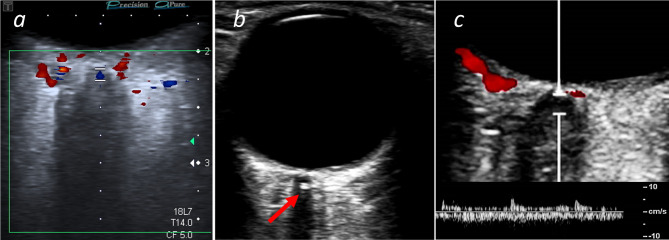

Background: Ischemic stroke (IS) and retinal ischemia (IR) share similar vascular risk factors, but differ in their risk for subsequent or recurrent stroke and therapeutic options. This study characterizes the cardiovascular risk profiles and magnitude of atherosclerosis of the carotid artery of patients with central retinal artery occlusion (CRAO) in relation to the presence of the retrobulbar "spot sign" on orbital color-coded sonography (OCCS).

Methods: We performed a retrospective analysis on the detailed cardiovascular risk factors and neuroimaging data in patients with IR presenting between 2009 and 2023. Based on OCCS findings, CRAO were further divided into hyperechoic ("spot sign positive", ssCRAO) or hypoechoic CRAO (heCRAO). Statistical analyses were performed with Mann-Whitney-U and χ [2] testing. P-values were considered significant if < 0.05.